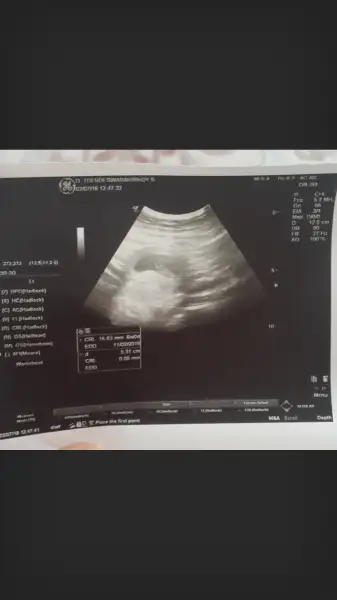

Progestan aliyon muKızlar kahverengı lekeler gelıyo benden çok korkuyorum

Hayırlısı olsun canım, darısı başıma inşallah. Resmin kenarları hiç okunmuyor, büyütünce çözünürlük gidiyor.Canlarr geldim hastaneden 8 haftalik dedi. Devlet hastanesi diyemi bilmem ama ses bozukmus cok az geliyodu onuda anca doktor duydu. Dedim aman siz duyunda yeterli yeterki olsun. 120_160 arasi dedi. Hemen 2. Tarama testi tarihide verdiler 1 ay sonraya. Resmin kenarlarinda yazanlar ne ifade ediyo.bilen varmiEki Görüntüle 2164145

Hayırlısı olsun canım, darısı başıma inşallah. Resmin kenarları hiç okunmuyor, büyütünce çözünürlük gidiyor.

HADİ GÖZÜN AYDIN ÇOK SEVİNDİM. DARISI BEKLEYEN ARKADAŞLARA.Canlarr geldim hastaneden 8 haftalik dedi. Devlet hastanesi diyemi bilmem ama ses bozukmus cok az geliyodu onuda anca doktor duydu. Dedim aman siz duyunda yeterli yeterki olsun. 120_160 arasi dedi. Hemen 2. Tarama testi tarihide verdiler 1 ay sonraya. Resmin kenarlarinda yazanlar ne ifade ediyo.bilen varmiEki Görüntüle 2164145